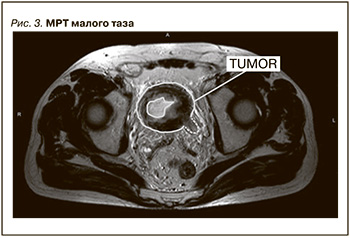

МРТ малого таза с внутривенным контрастированием: МП туго не заполнен, содержимое его неоднородное. На T2-взвешенном изображении визуализируется асимметричное инфильтративное утолщение левой стенки МП, экзофитно растущее в просвет МП объемное образование на широком основании с инвазией в мышечный слой стенки, левое устье, не распространяющееся за пределы МП. В нижней трети левого мочеточника на 15 мм от устья отмечается рост данного образования (рис. 3).